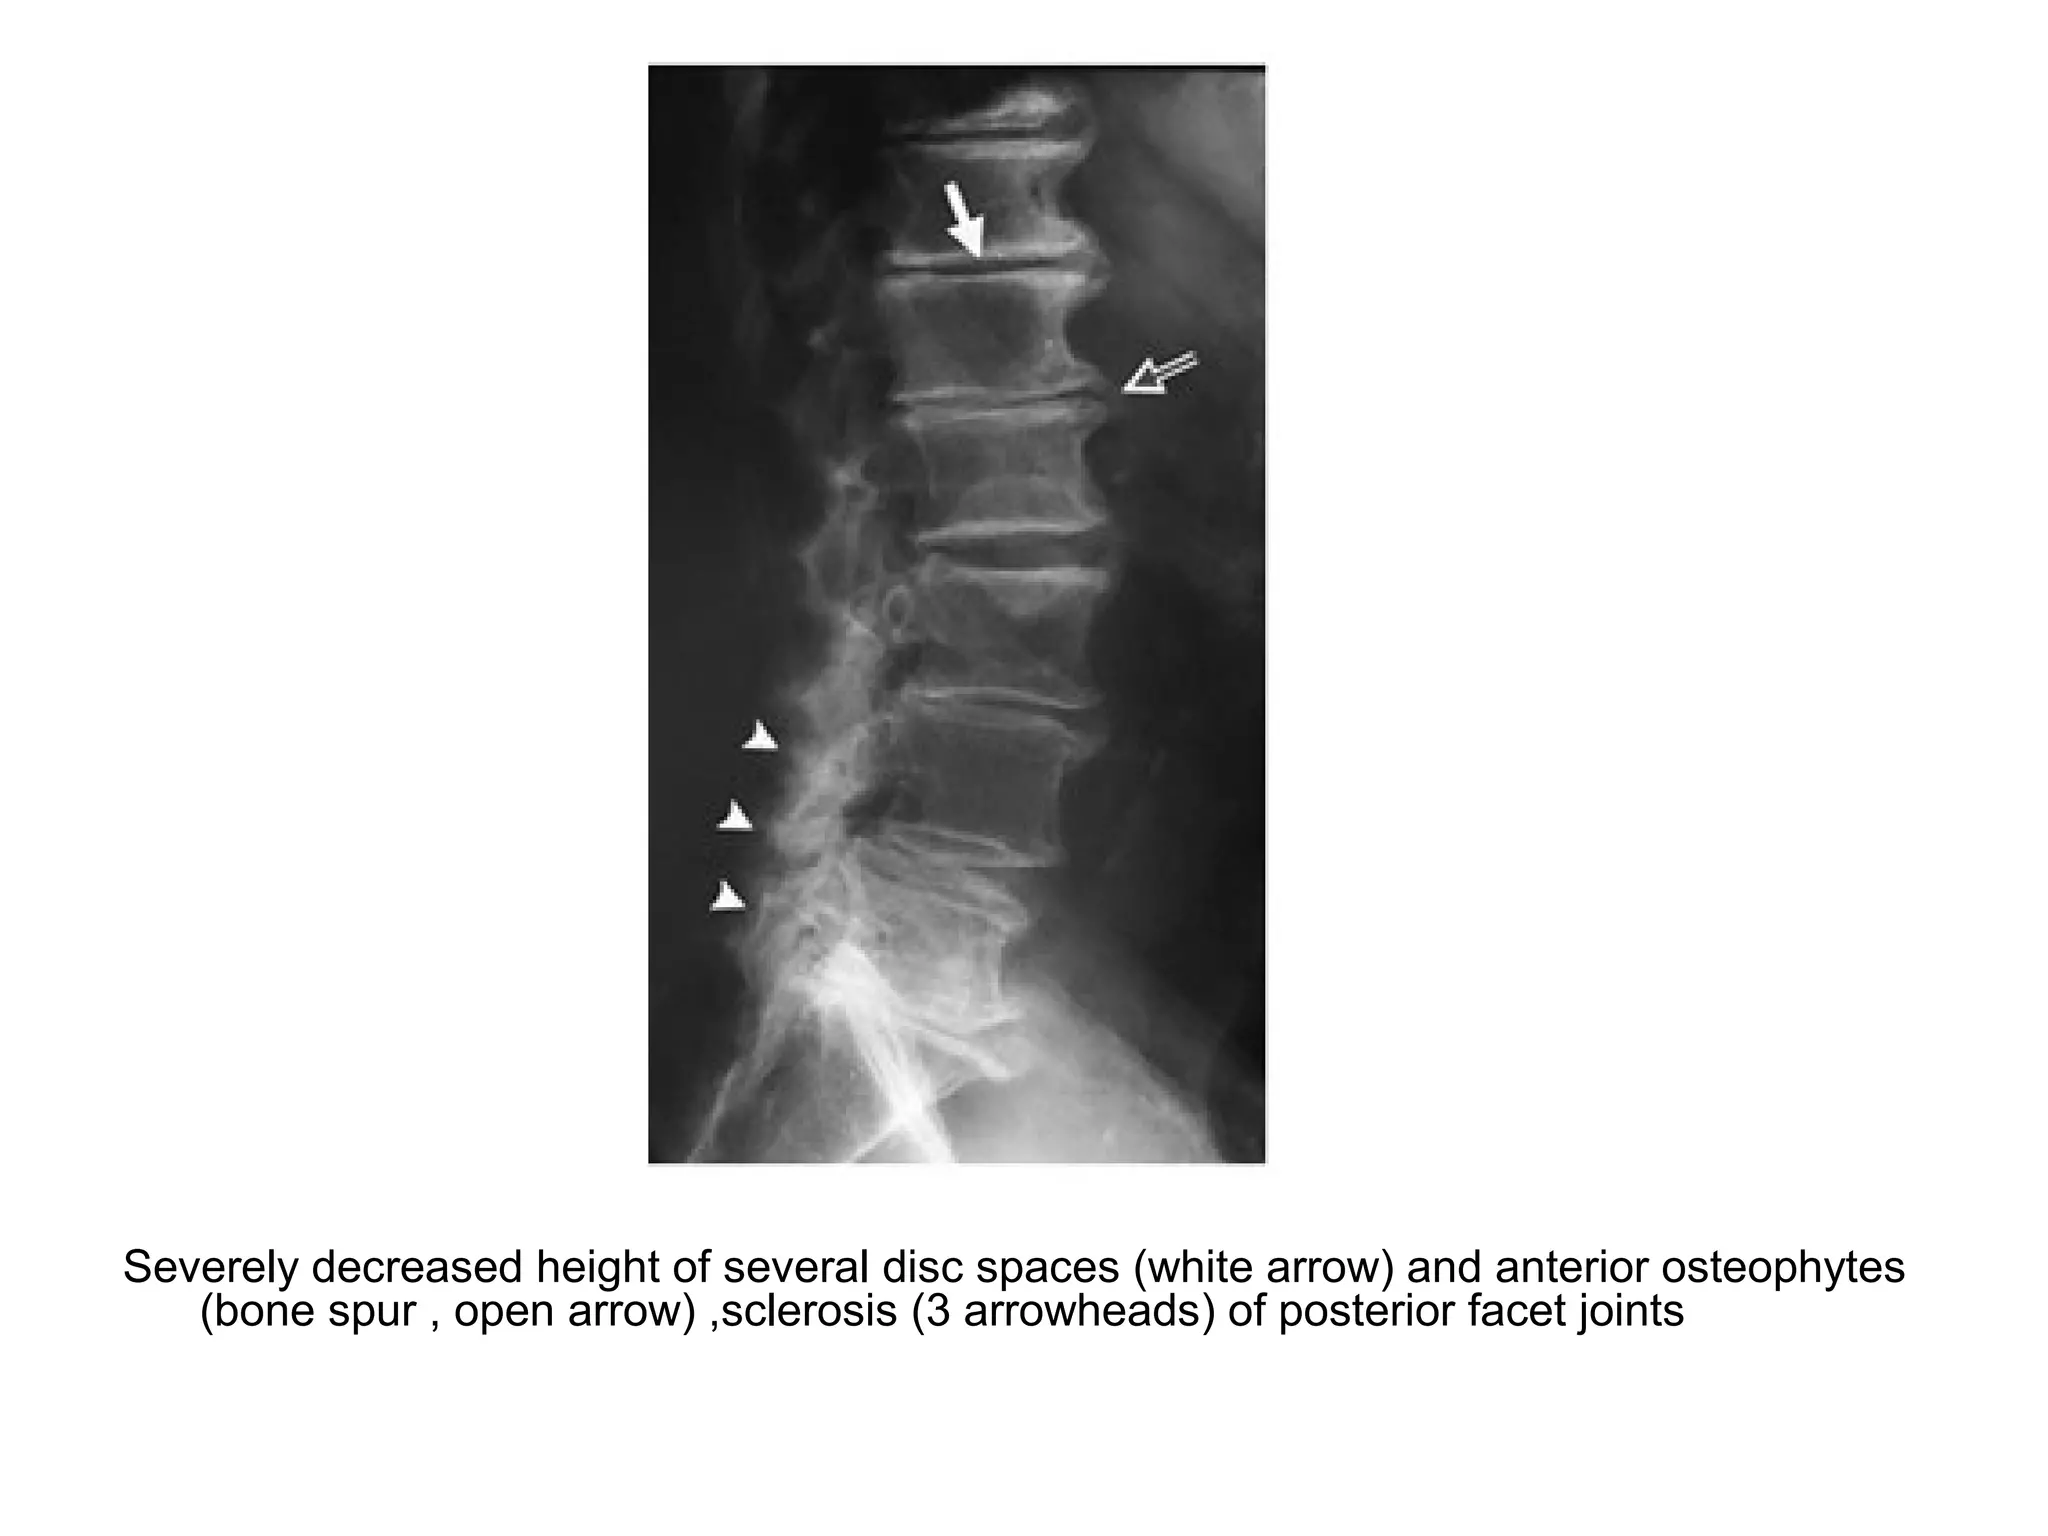

Severely decreased height of several disc spaces (white arrow) and anterior osteophytes

(bone spur , open arrow) ,sclerosis (3 arrowheads) of posterior facet joints